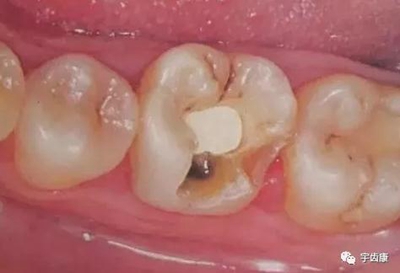

防止過度預(yù)備(造成牙髓激惹)

過度預(yù)備抗力形喪失

8. 實際備牙產(chǎn)生的問題